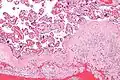

| Micrograph of a chronic deciduitis, showing the characteristic plasma cells. H&E stain. | |

Chronic deciduitis is a type of long-lasting inflammation that arises in pregnancy and affects the endometrial stromal tissue (decidua).

It is associated with preterm labour.[1] The diagnosis rests primarily on the presence of plasma cells.[2]